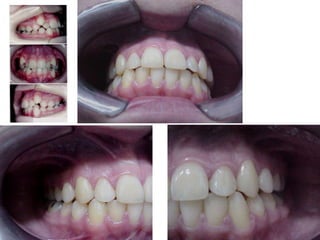

O documento descreve um caso de apinhamento dentário tratado sem extrações. O paciente apresentava asma, respiração bucal e língua hipotônica devido ao apinhamento. O tratamento envolveu remodelação dos dentes sem extrair nenhum, corrigindo o desvio de linha média.